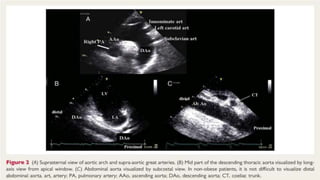

ECHOCARDIOGRAPHY

● Evaluation of the aorta is a routine part of the standard echocardiographic

● Transthoracic echocardiography (TTE) permits adequate assessment of several

● TOE overcomes the limitations of TTE in thoracic aorta assessment

● TTE & TOE should be used in complementary manner.

Transthoracic echocardiography

● Using different windows , The Proximal ascending aorta is visualized in the left

and right parasternal long axis view.

● In all patients with suspected aortic disease the right parasternal view is

● Modified subcostal views may in some cases (more in children) be helpful , but

● All these views also permit assessment of the Aortic valve , which is often

● From this windows aortic Coarctation can be visualized and functionally

evaluated by continous-wave by colour doppler.

● Dilatation and Aneurysm, plaque , calcification, thrombus or a dissection

membrane are detectable if image quality is sufficient